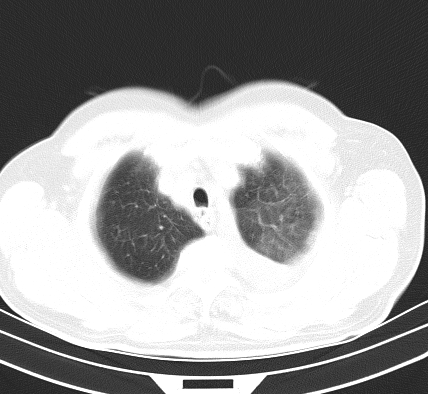

以下是引用老爱克斯新网客在2008-7-31 6:30:00的发言:[br]左肺上叶大片状病灶,左肺上叶支气管狭窄呈鼠尾状,左肺门增大,纵隔内见肿大淋巴结,左侧胸腔积液,余肺清晰。左肺中心型肺癌淋巴结转移,

以下是引用zjb在2008-7-31 6:32:00的发言:[br]左侧中心性肺癌 阻塞性肺炎 肺不张 胸腔积液 建议气管镜

以下是引用zjzjr在2008-7-31 8:45:00的发言:[br]考虑左侧中心性肺癌伴阻塞性肺炎,左肺上叶肺不张,纵隔淋巴结转移;左侧胸腔积液。建议行纤支镜检查。

以下是引用sdzyy在2008-7-31 8:47:00的发言:[br]病灶较治疗前有所进展,胸水增多, 左侧中心性肺癌 并 阻塞性肺炎 肺不张 胸腔积液 可能性大; 建议气管镜检查。 [br] [br]